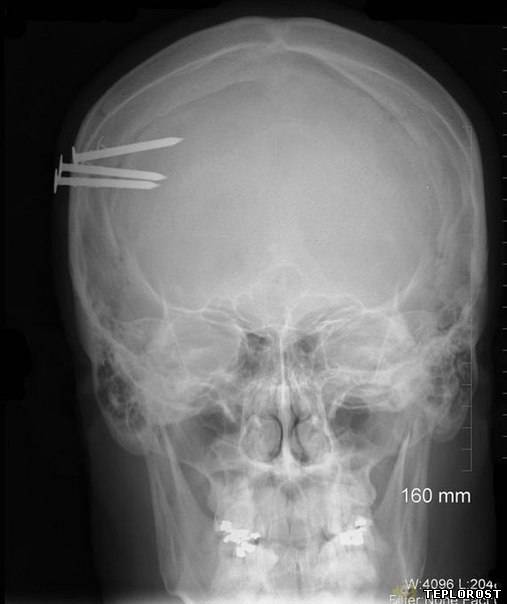

Гвозди в черепе человека.